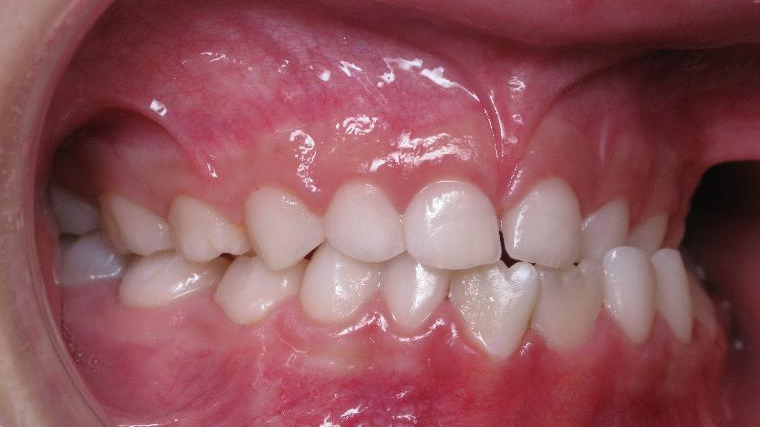

9. inversé gauche 6 ans

inversion des dents posterieur cote gauche